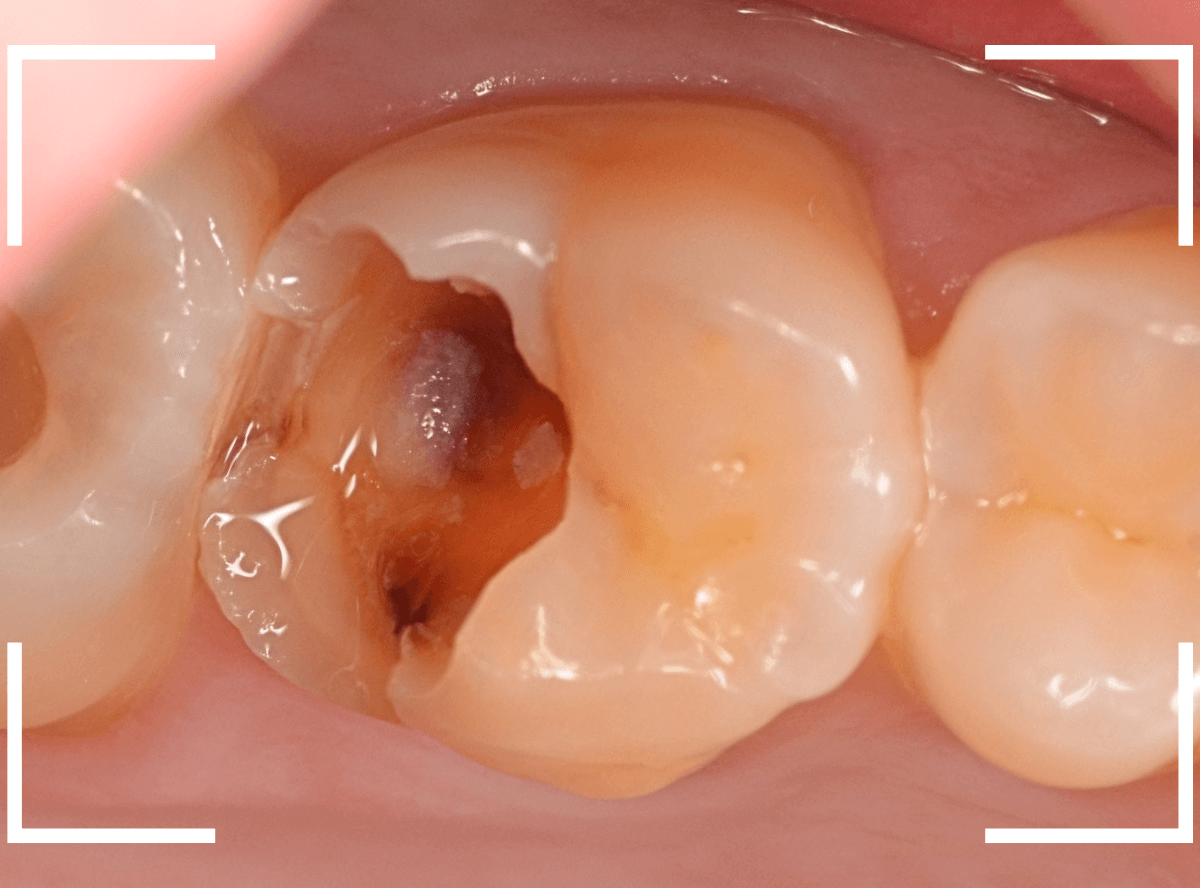

直近の患者さんの例で説明しましょう。

3本の大きな虫歯を除去した後に、ベースセメントで歯を保護します。

ここでこのまま、つめものが入るように歯をトリミングして型どりをしてもいいのですが、症状が出ないかしばらく経過観察します。

症状がないのを確認できたら、改めて歯のトリミングをして型どりをして、つめものをsetします。

この方法は、来院回数がかかりますが、症状がない事を確認してからつめものを作るステップに入るために、その後のトラブルは非常に少ないと感じています。

実際に使っている場面です。

虫歯の治療のブログでも紹介した症例ですが、レントゲン写真で、破折したレジンの中で神経の近くまで虫歯になっているのがわかります。

神経に近い虫歯ですので、いつも以上に慎重に虫歯をある程度除去したところで、虫歯の状況を検知液で確認します。